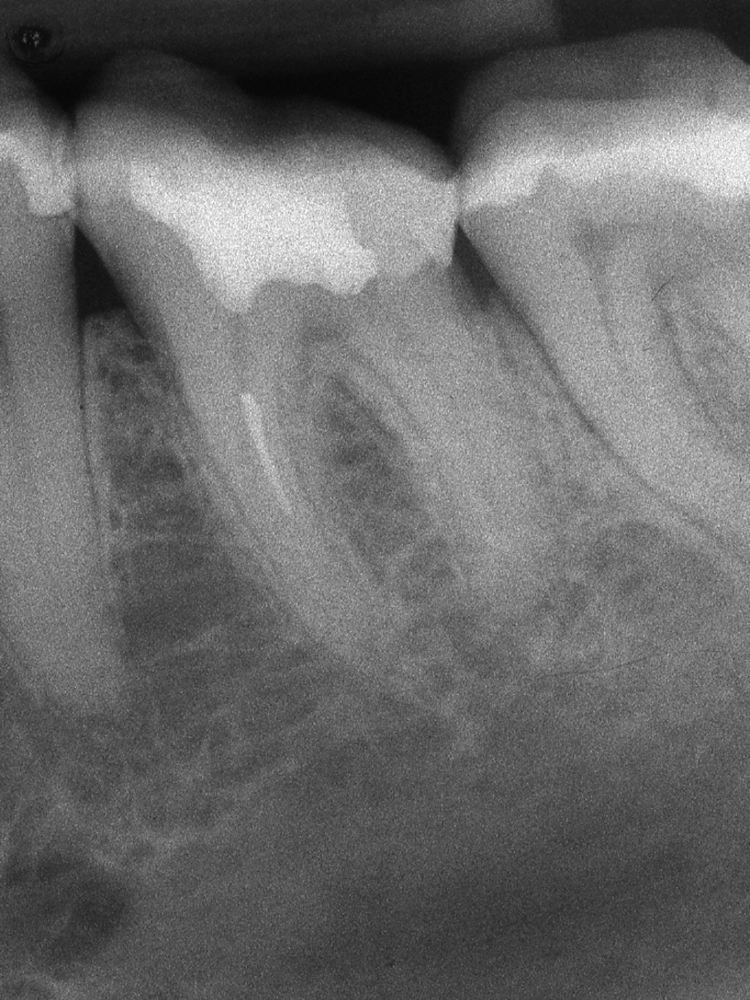

Das Risiko eines Instrumentenbruches ist an einem Molaren signifikant größer als an einem Prämolaren [5]. Die Zugänglichkeit der Wurzelkanaleingänge, die Krümmung sowie der Durchmesser der Wurzelkanalhohlräume sind dabei maßgebliche Faktoren [14]. Am häufigsten frakturieren Aufbereitungsinstrumente in den mesiobukkalen Wurzelkanälen von Molaren.

Die Schwierigkeit der mechanischen Ausformung eines Wurzelkanals steigt mit zunehmendem Krümmungswinkel und abnehmendem Krümmungsradius an (Abb. 1). Eine koronale Lokalisierung der Krümmung erhöht die Wahrscheinlichkeit einer Instrumentenfraktur im Vergleich zu einer Krümmung des Wurzelkanals im mittleren oder apikalen Wurzeldrittel [2] (Abb. 2).

Trotzdem verbleiben die meisten Fragmente im apikalen Wurzeldrittel (52,5%). Im mittleren Wurzeldrittel erfolgen 27,5% und im koronalen Wurzeldrittel 12,5% der Frakturen [15].